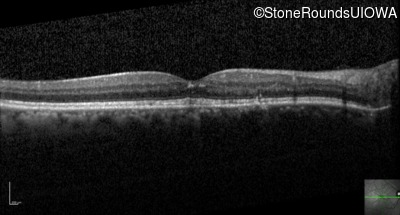

Optical Coherence Tomography - Right - 20/20

Exemplar / OCT Stack